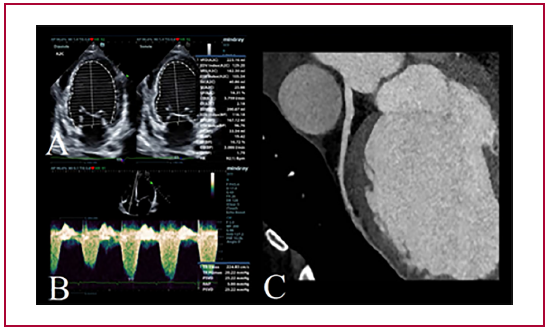

Miocardiopatía dilatada y distrofia muscular de Duchenne